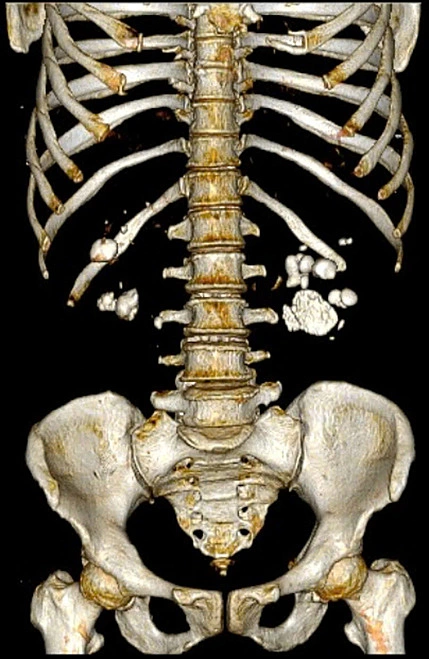

Ảnh chụp CT sỏi bám chi chít trong hai quả thận người phụ nữ. Ảnh: Bác sĩ cung cấp

Bà từng phẫu thuật mổ mở sỏi thận cả hai bên nhưng không tái khám,gần đây đau dữ dội mới đến bệnh viện. Ngày 29/12,bác sĩ Mai Văn Lực,khoa Ngoại Tiết niệu và Nam học,Bệnh viện E Hà Nội,cho biết "thận bệnh nhân gần như hỏng hoàn toàn". Siêu âm cho thấy hai quả thận bị tổn thương nghiêm trọng,đài bể thận biến dạng,giãn căng,chức năng suy giảm nặng,trên nền vết mổ cũ có rất nhiều sỏi li ti bám dày đặc.

"Đây là một trong những ca sỏi thận phức tạp,nguy cơ mất thận rất cao nếu xử lý không cẩn trọng",bác sĩ Lực nhận định.